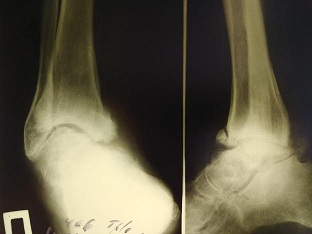

3. рис.2 | |

| Тема | ||

| Тип | author.submit.suppFile.figureResearchMaterials | |

Посмотреть

(75KB)